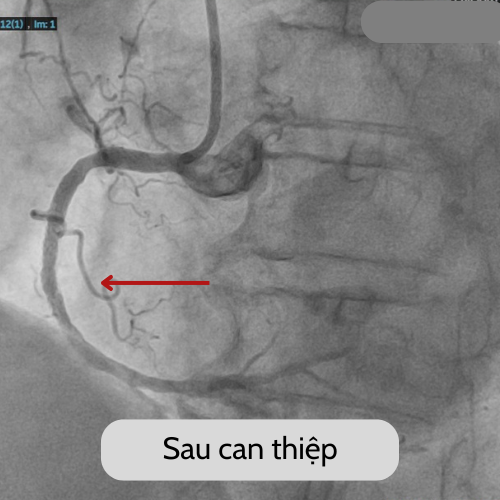

| Hình ảnh trước và sau can thiệp của bệnh nhân G - Ảnh BVCC |

Kết quả chụp mạch vành ghi nhận tắc hoàn toàn đoạn giữa động mạch vành phải. Với bệnh cảnh này, các bác sĩ khoa Nội tim mạch BVĐK Xuyên Á Long An đã quyết định thực hiện can thiệp nong và đặt stent tại vị trí tổn thương tắc mạch. Ca can thiệp đã được diễn ra nhanh chóng với kết quả thành công tốt đẹp. Những triệu chứng nặng ngực của người bệnh đã cải thiện nhanh chóng, sức khoẻ ổn định và được xuất viện sau vài ngày theo dõi.